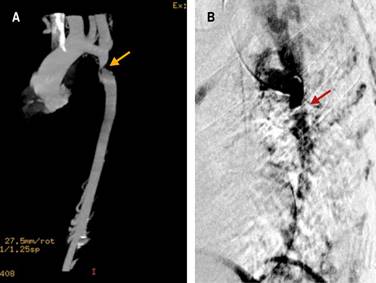

Figure 1: Reconstructed CT aortogram showing localized narrowing of the aorta. A) Reconstruction of the coronal angio-tomography, the projection shows the coarctation site that is 21 mm from the left subclavian artery. B) Digital subtraction angiography showing the thoracic aorta with coarctation.